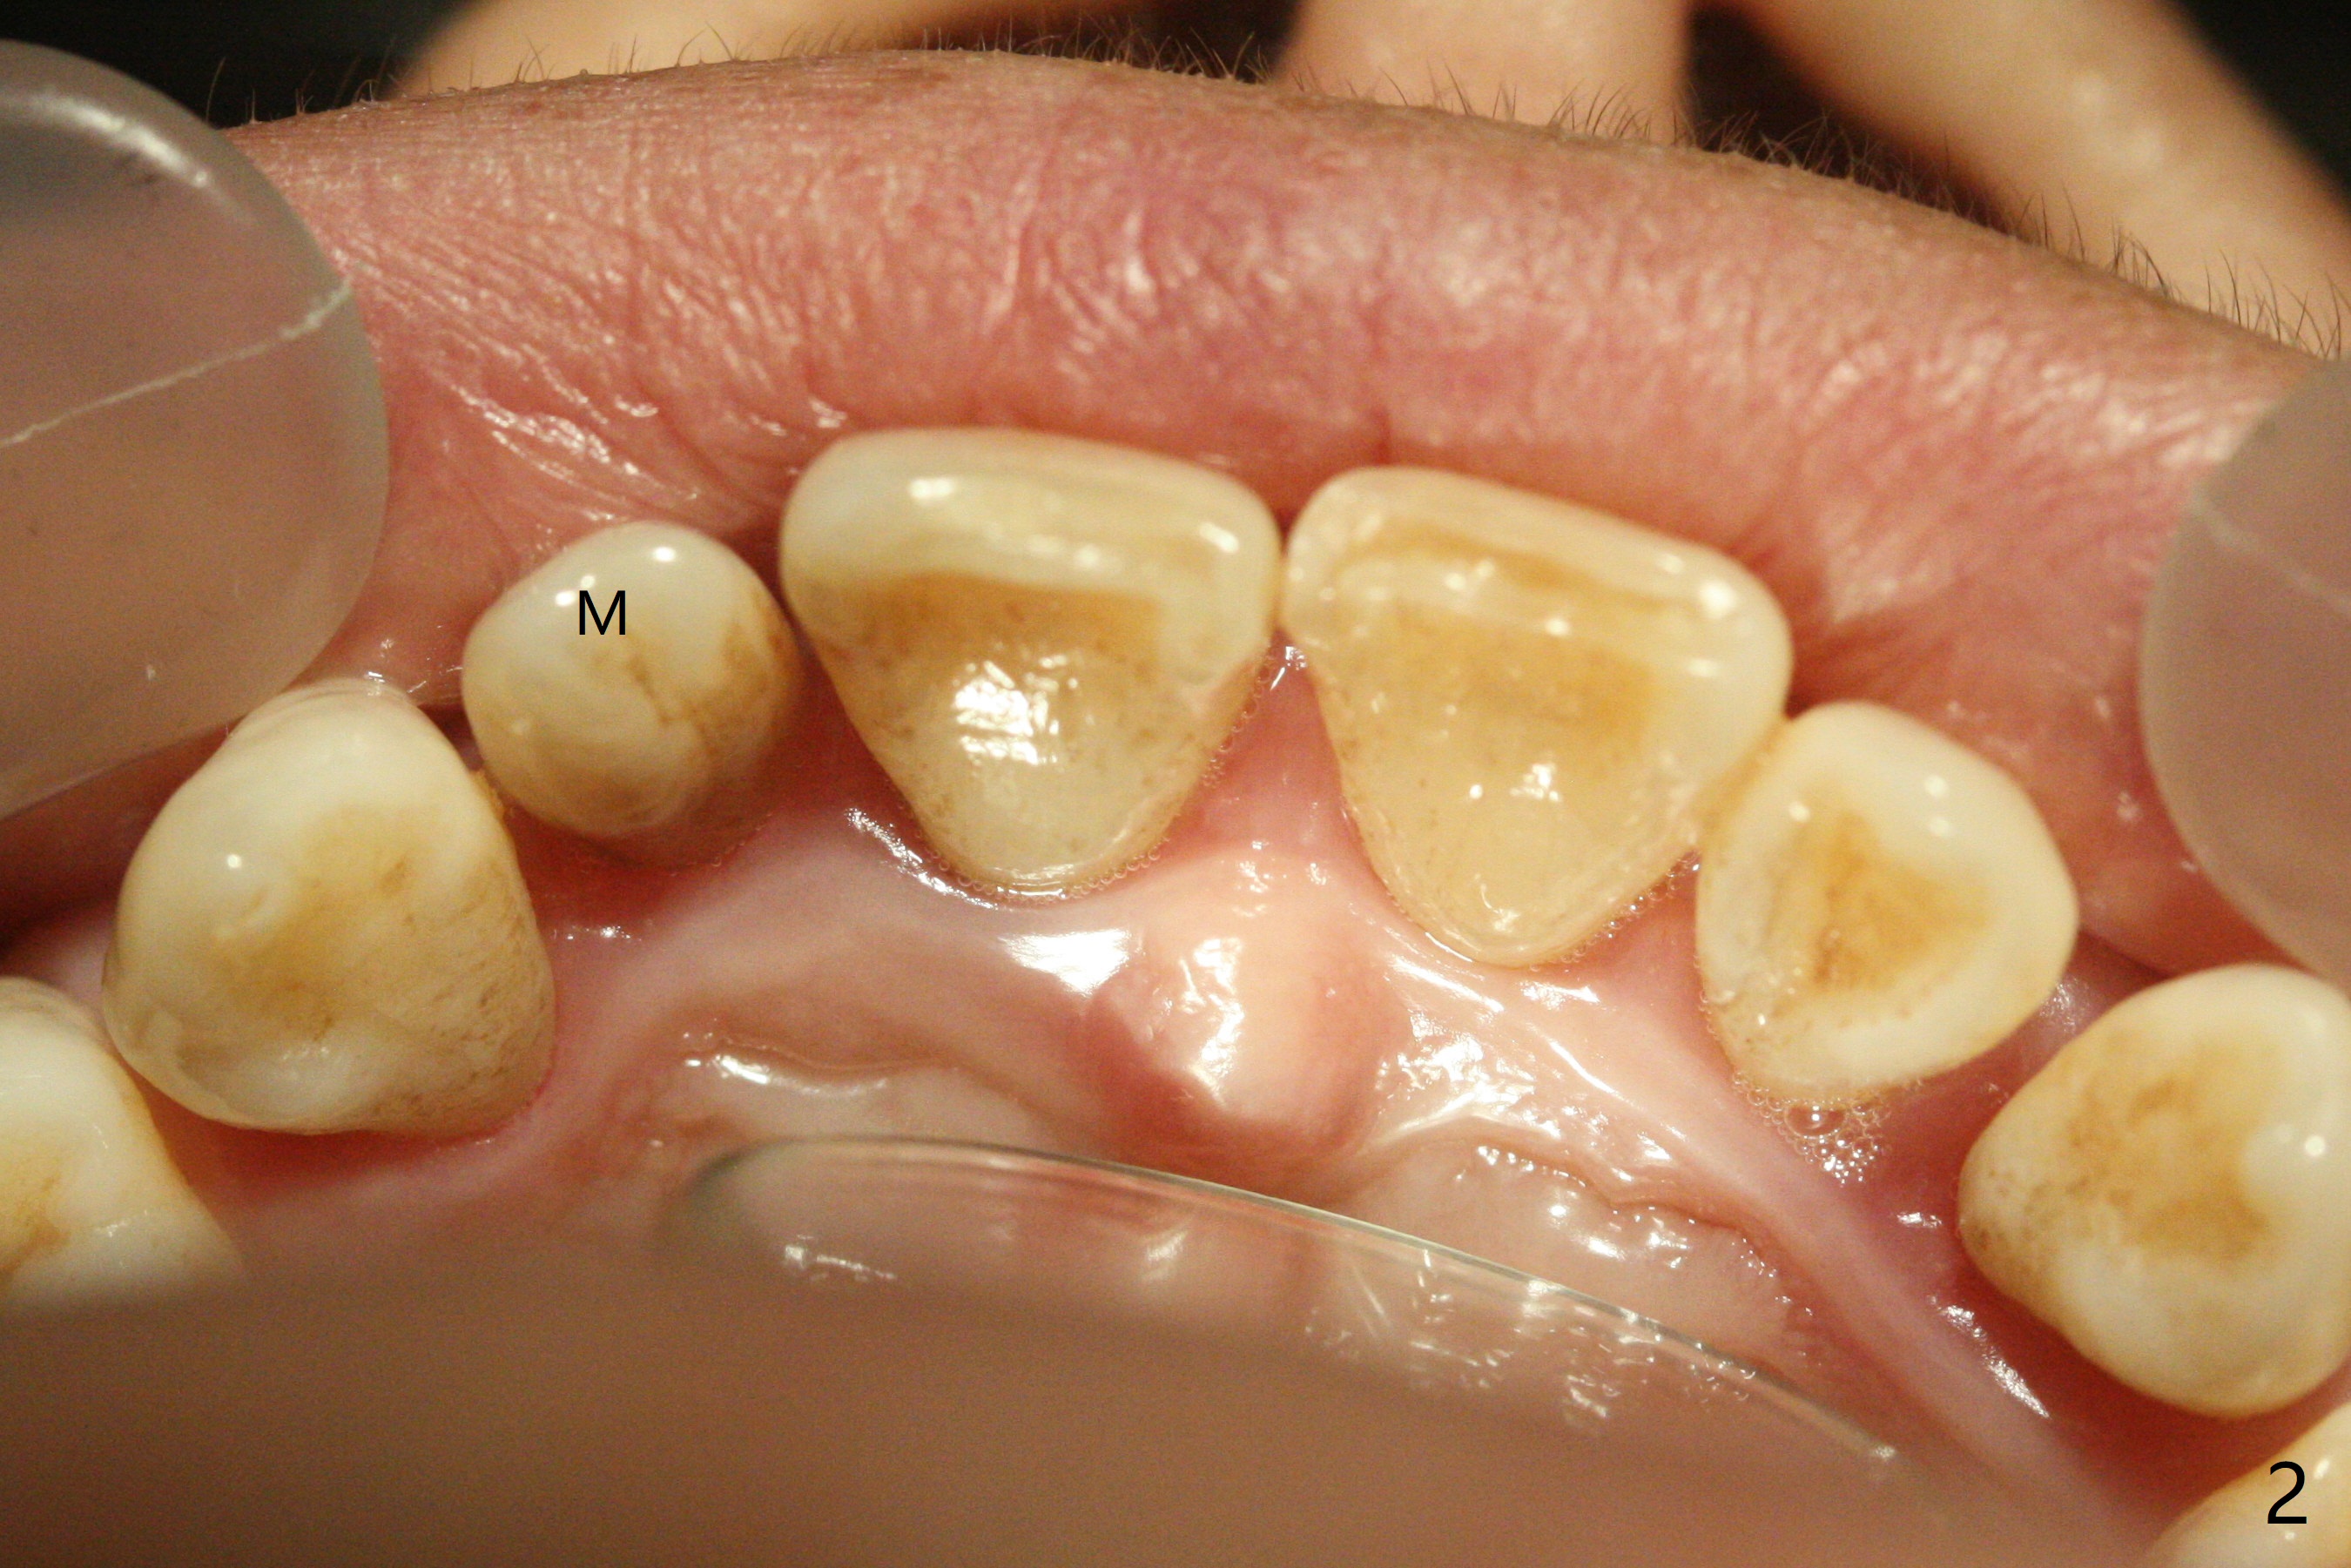

A 45-year-old woman presented to office for new patient examination. The latter reveals discoloration (Fig.1 necrosis on pulpal test; * labial concavity), microdontia with possible root canal malformation (Fig.2: M) and large inverted pear-shaped cyst (Fig.3) of the tooth #7. Guarded prognosis will be emphasized prior to treatment.